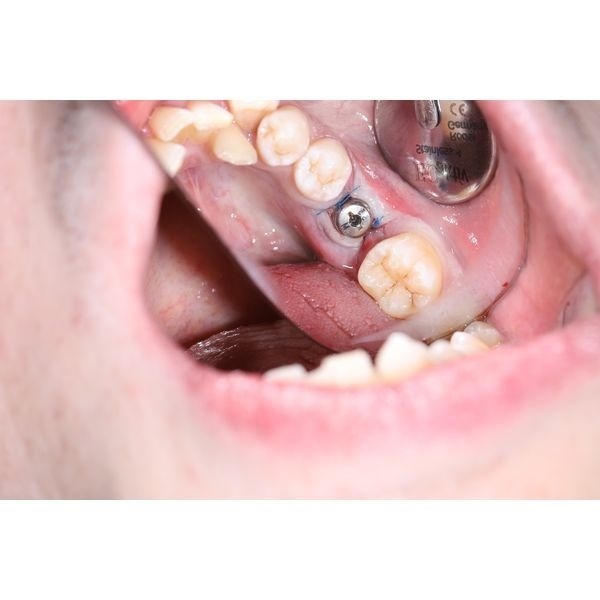

- установили имплантат Impro 5 × 10 и формирователь десны;

На следующий день пациент отмечал незначительные болевые ощущения и небольшую припухлость в области нижней челюсти слева. Через 2 недели сняли швы, а спустя 3 месяца его направили на протезирование имплантата к стоматологу-ортопеду. Врач снял слепки и изготовил циркониевые коронки на винтовой фиксации. Весь период лечения занял 4 месяца.